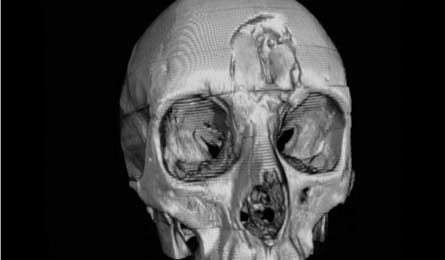

Fisch’s Skull

Injuries Frontal bone (forehead) fracture, six broken vertebrae, and a detached ear

Twelve hours later, two hikers found Brenna Fisch bleeding, hypothermic, and laying in the trail with a dent in her forehead. She stayed in the hospital for a month as doctors monitored her brain swelling and patched the fracture with a titanium plate, using IV antibiotics to ward off infection.